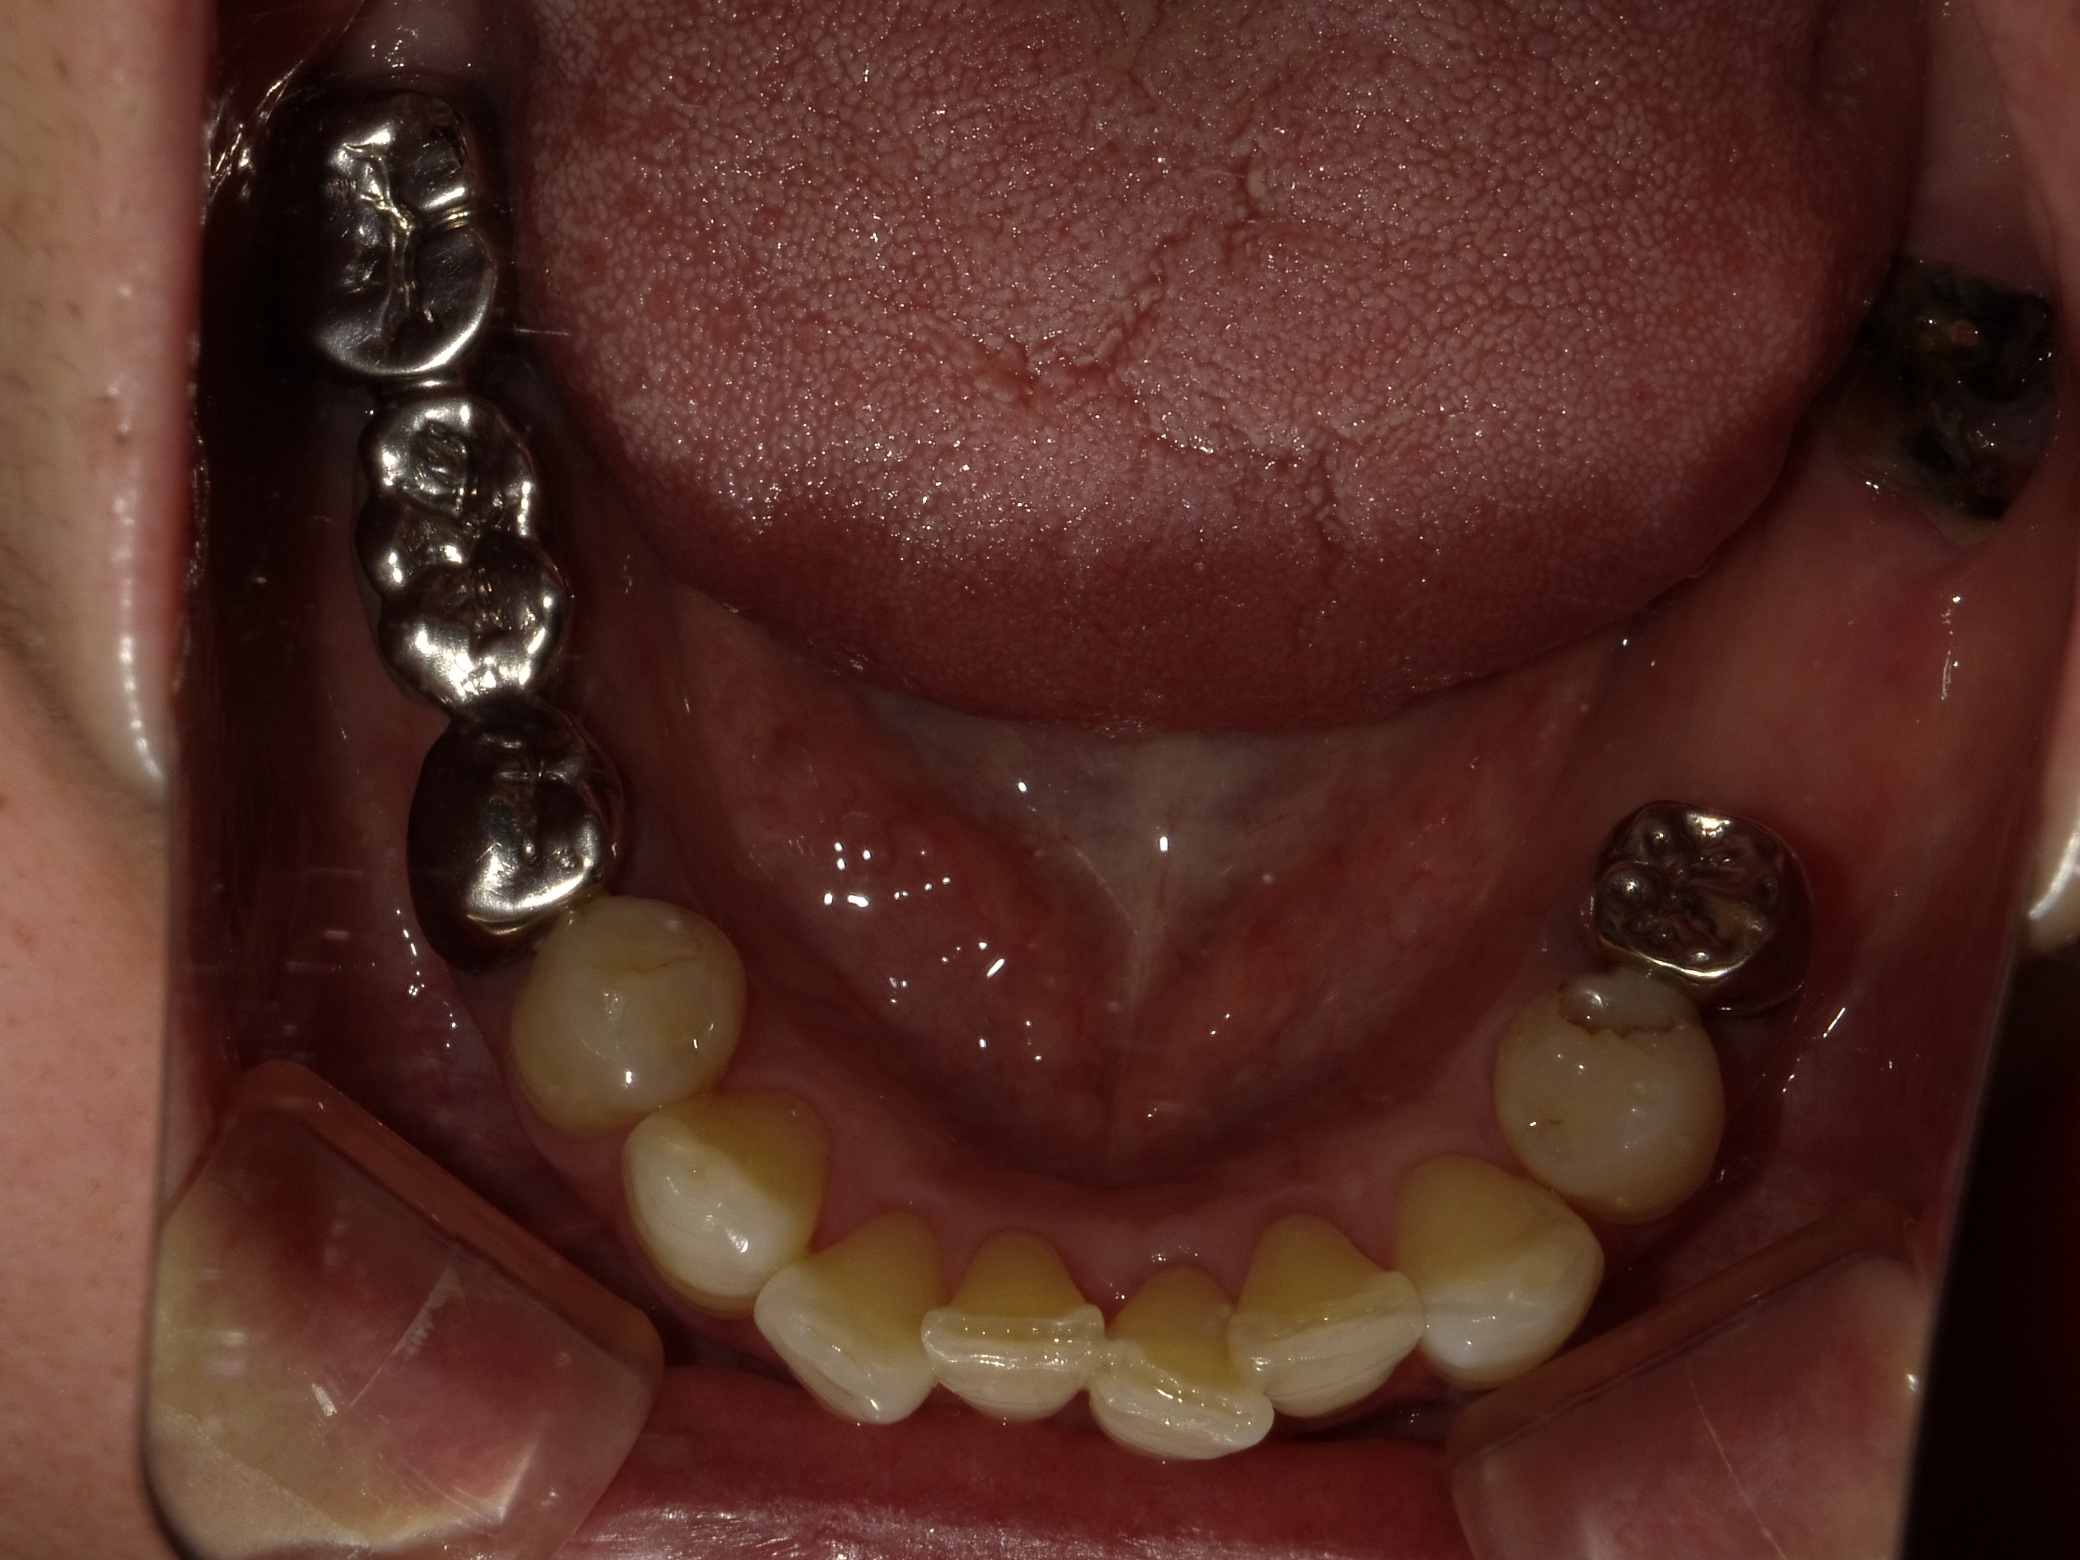

BEFORE

主訴

全体的に見た目を綺麗にしたい。奥歯でしっかり噛みたい。

診断名・主な症状

臼歯部欠損

年齢

70歳

治療内容

インプラント埋入(右上4・6,左上4・6,右下6,左下6)

ジルコニアBr(右上3―左上3)

ジルコニア(右下5,左下5)

治療期間/

通院回数

インプラント 1年5ヶ月/13回

ジルコニアBr、ジルコニアクラウン 3ヶ月/10回

費用

インプラント: 2,552,000円

その他治療: 640,000円

合計 3,192,000円

*いずれも税込